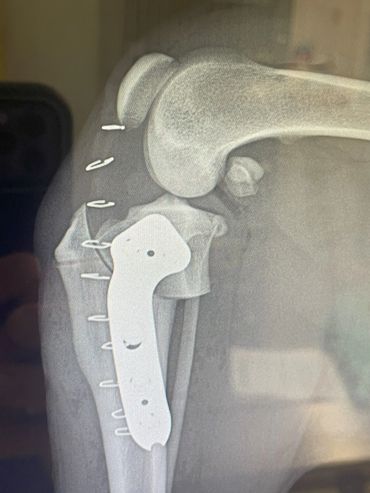

If your pet has a torn CCL they will usually be uncomfortable and manifest this as limping. They often prefer to limit their own activity level due to the pain and may be more sedentary. When a CCL tear is diagnosed, usually the best option is to stabilize the stifle surgically for the best outcome. One technique commonly performed for decades has been the Tibial Plateau Leveling Osteotomy (TPLO). The TPLO was designed to eliminate the tibial thrust motion that occurs with a CCL tear and thus return stability to the stifle for return to function. The TPLO procedure is very technical and thus is best performed by experienced surgeons. Initially the TPLO was only taught by the original designer of the procedure, Slocum Enterprises, and luckily Dr. House managed to complete this training program before it ended. To perform a TPLO procedure a bone cut (osteotomy) is made in the shin bone (tibia) near the knee. This cut is curved and allows a change in the angle within the stifle to alter the forces as mentioned above. Once the cut is made and the bone is rotated, a metal plate and screws are placed to hold the bone in its new position while it heals. These implants are usually left in place for life and are only removed if a reaction or infection should develop, which is generally uncommon. Since a cut is made in the bone for this procedure, patients must go through a rest period while the bone heals adequately for normal activity again. It is critical that patients rest to avoid breaking their bone or the implants. The post-operative instructions typically followed are below. If your pet has been diagnosed with a CCL tear, a TPLO may be recommended. This procedure is usually best performed in pets weighing 50 pounds and above. It can be performed in animals under 50 pounds, however, and this can be determined at a surgical consultation. Dr. House performs the TPLO procedure almost daily and would be happy to meet with you and your pet to discuss and perform the procedure accordingly at your local veterinary clinic.